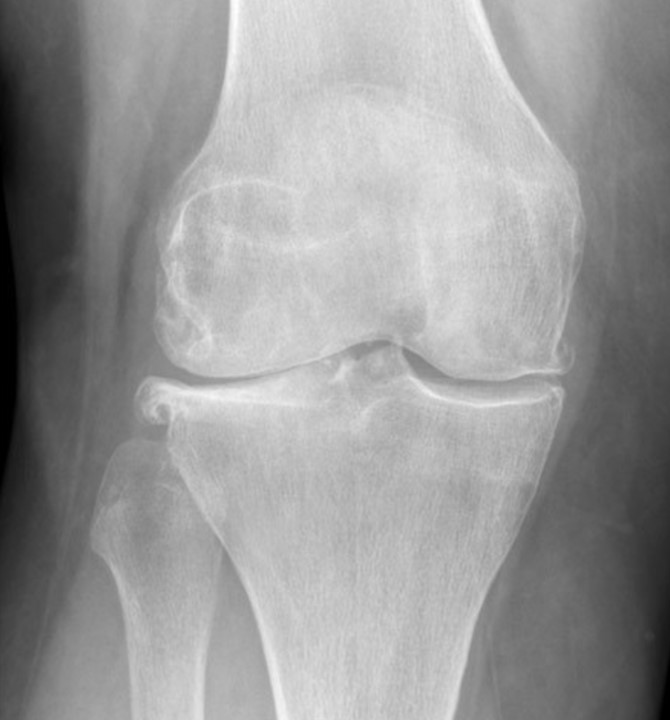

骨關節炎是最常見的關節炎,全球有數百萬的人們患有此病。隨著時間推移,骨骼末端起緩衝作用的保護性軟骨不斷磨損,就會發生該疾病。

雖然骨關節炎可能損害任何關節,但疾病最常影響膝蓋、髖關節和脊柱中的關節。

雖然關節損傷是不可逆的,但骨關節炎的症狀通常可進行控制。保持活動狀態、維持健康體重和接受幹細胞治療可減緩疾病進展,並有助於改善疼痛和關節功能。